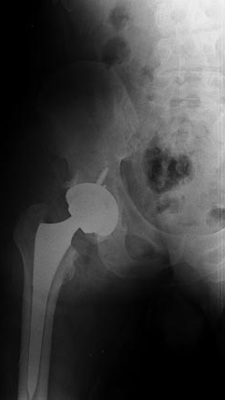

Total Hip Replacement of Ball and Socket